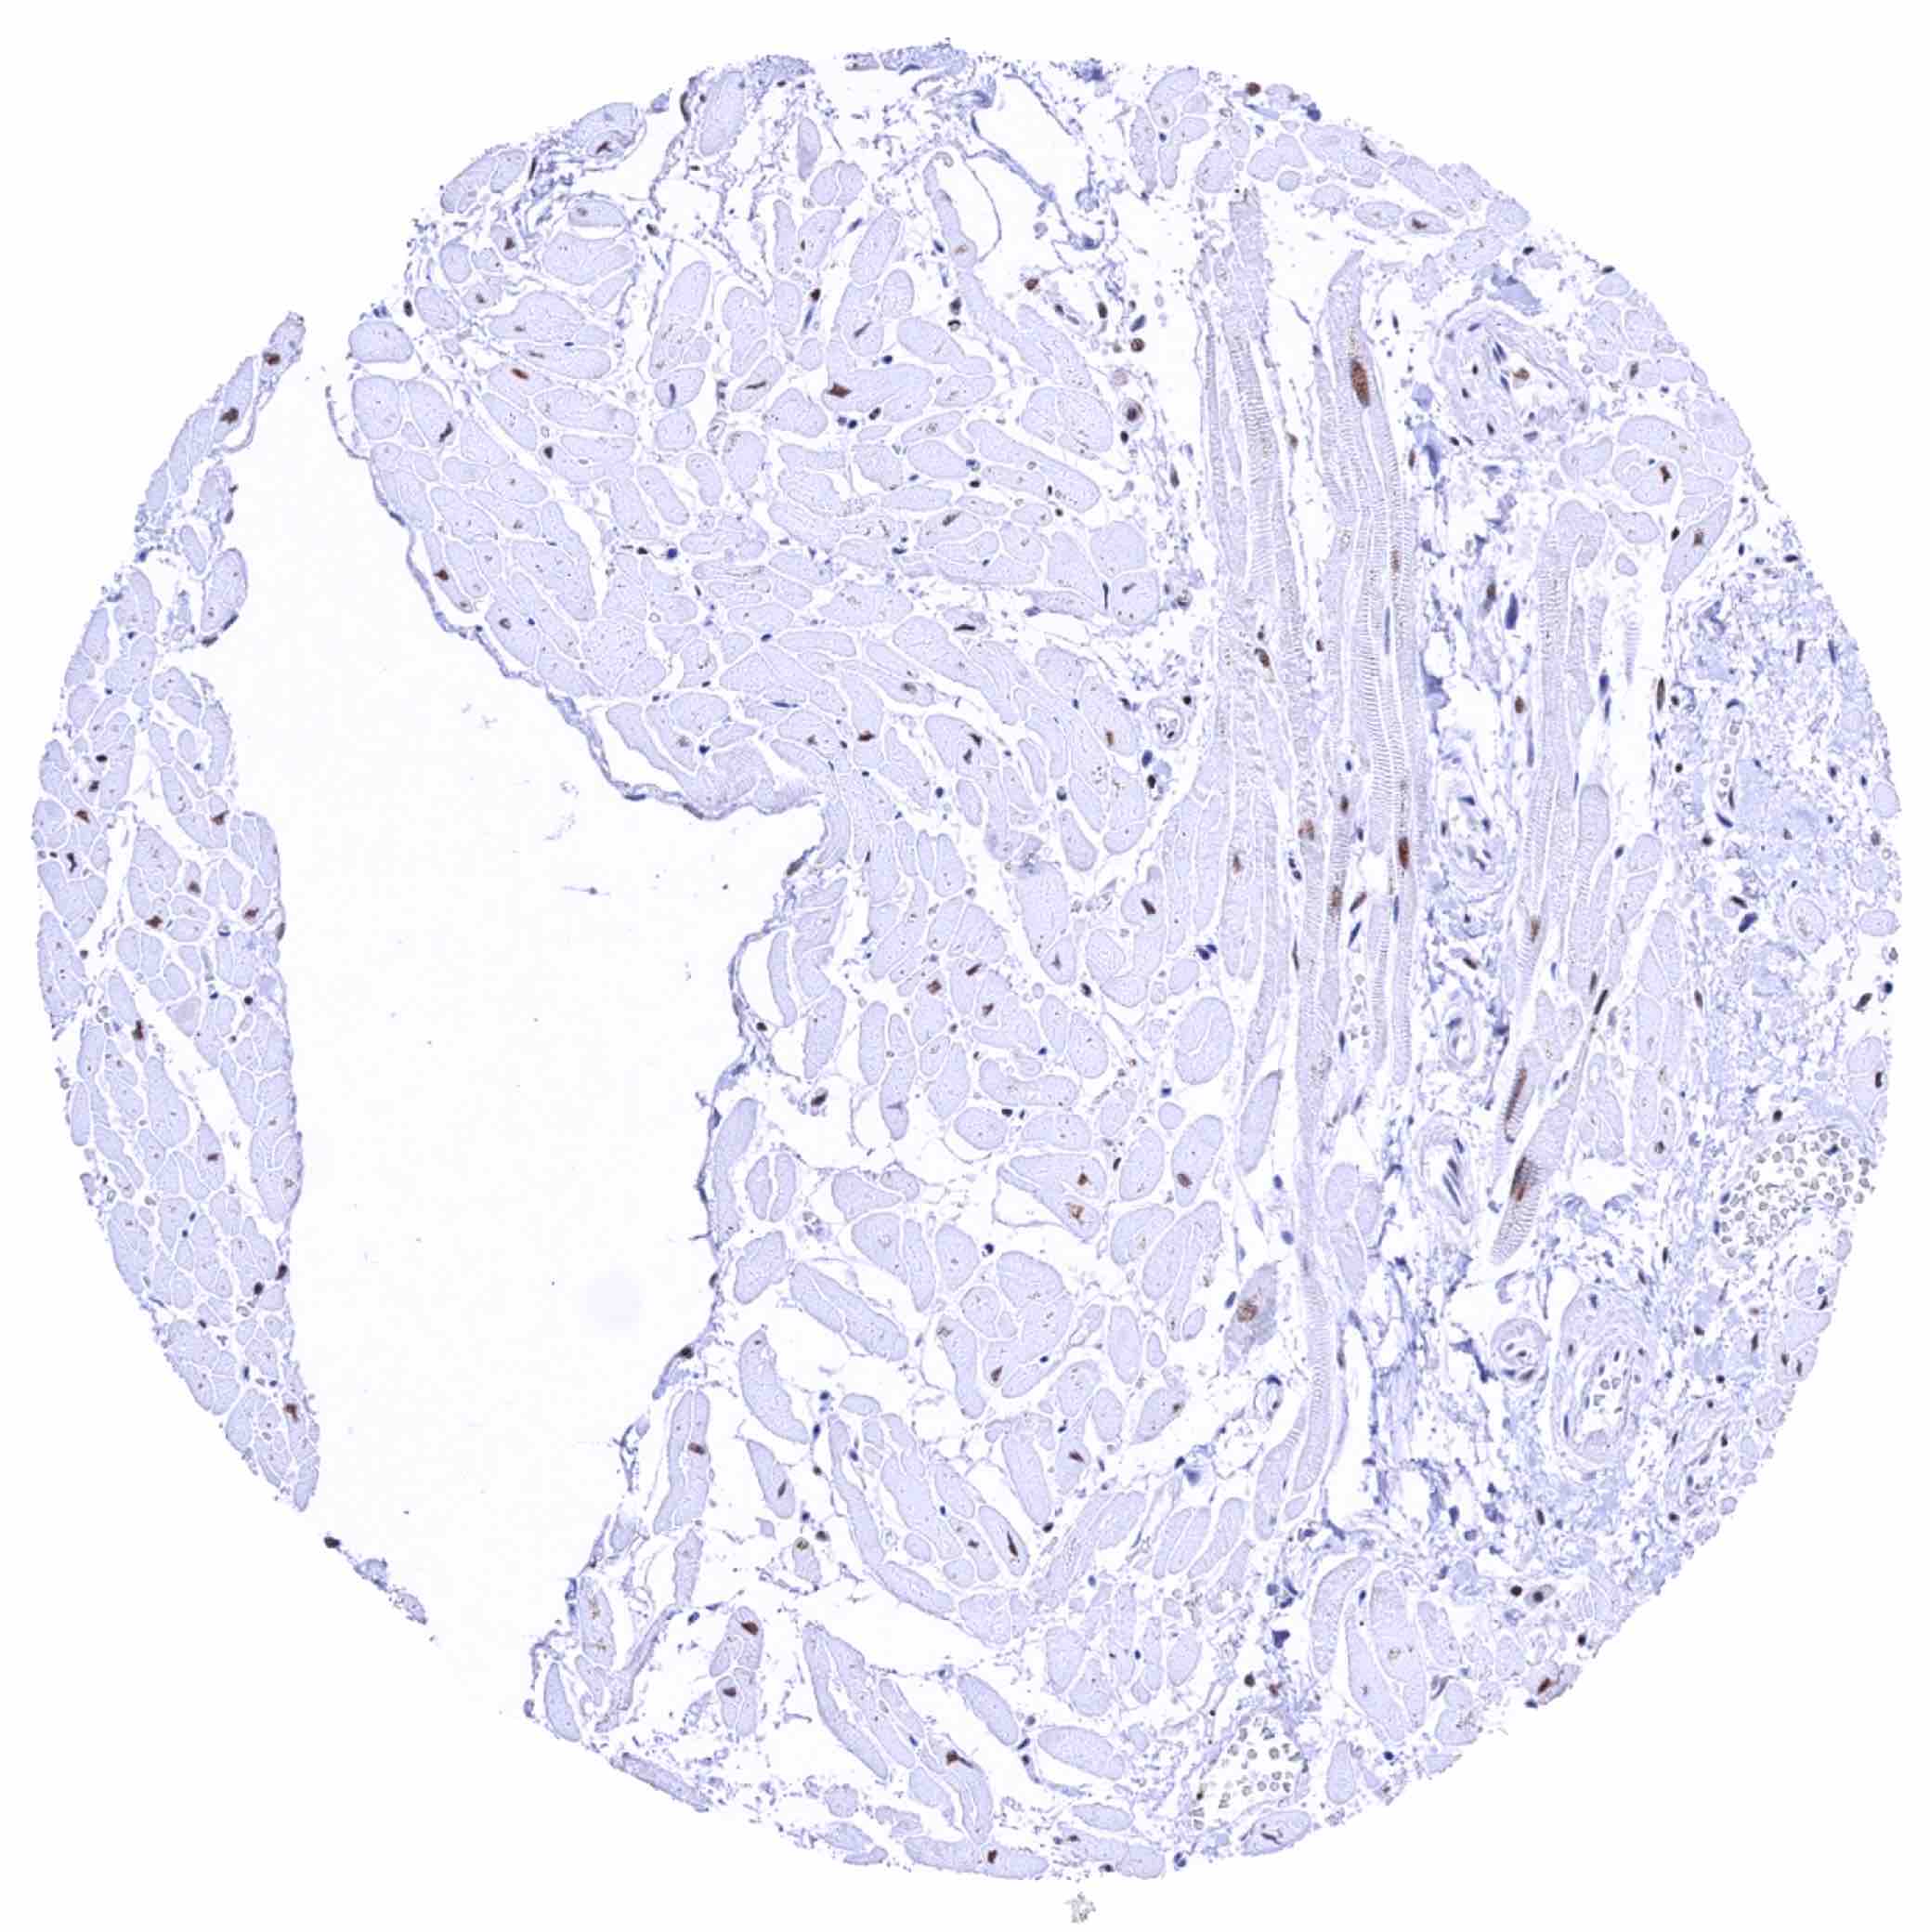

Skeletal muscle – Moderate nuclear KDM6A staining of muscular cells